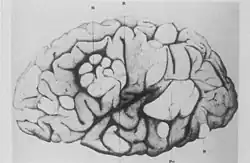

Ces anomalies sont en rapport avec une atteinte du cortex cérébral sous la forme d'« hamartomes tubers », correspondant à une désorganisation de la structure en couches (les circonvolutions sont anormalement grandes et on a perte de l'agencement des neurones), avec prolifération de cellules géantes pouvant se manifester par des tumeurs de type astrocytomes[8] et/ou nodules sous-épendymaires. On les retrouve souvent dans la région du foramen de Monro. Ces tumeurs, bien que bénignes, ont tendance à récidiver si une ablation chirurgicale complète ne peut être effectuée. Une dégénérescence kystique est possible.